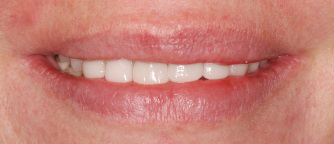

Cas 5 : Combinaison de facettes + couronnes